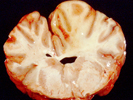

Figure 11 |

The fumonisins are a group of mycotoxins produced primarily by Fusarium verticillioides and Fusarium proliferatum, although a few other Fusarium species also may produce them. Traditionally, Fusarium moniliforme is the fungal species associated with fumonisins, but this name is no longer used, due to advances in taxonomy and nomenclature. There are at least 28 different forms of fumonisins, most designated as A-series, B-series, C-series, and P-series. Fumonisin B1 is the most common and economically important form, followed by B2 and B3. Maize is the most commonly contaminated crop, and fumonisins are the most common mycotoxins in maize, although these toxins can occur in a few other crops as well. Fusarium verticillioides and fumonisins are distributed worldwide. The primary health concerns associated with fumonisins are acute (single exposure) toxic effects in horses and swine, and carcinogenic (able to cause cancer) properties. Horses that are poisoned with fumonisins may develop a fatal disease known as equine leukoencephalomalacia. Symptoms of this disease include drowsiness, blindness, staggering, and liquefaction of brain tissue [Figure 9]. Swine that are poisoned with fumonisins may experience reduced feed intake and weight gain, liver damage, and can develop a fatal disease known as pulmonary edema, in which the animals' lungs are filled with fluid. Fumonisins are carcinogenic to laboratory animals, and in humans, consumption of fumonisin-contaminated maize is associated with higher rates of esophageal cancer and neural tube birth defects. Fumonisins were first characterized in the late 1980s, as a result of studies into the causes of esophageal cancer in Africa, coupled with outbreaks of equine leukoencephalomalacia and porcine pulmonary edema in the U.S.